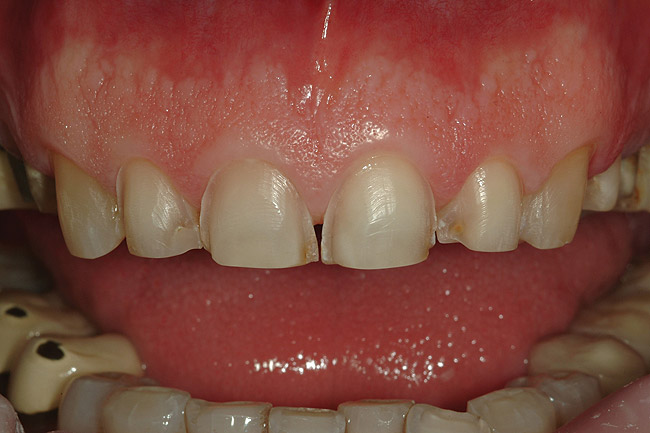

A 50-year-old, highly stressed businessman presented with severe wear on all teeth. The excessive wear developed over time because of a combination of age and malocclusion (Figure 1 and Figure 2). After the initial examination and consultation, the patient agreed to treatment in three phases using lithium-disilicate all-ceramic restorations (IPS e.max® Press, Ivoclar Vivadent, www.ivoclarvivadent.com). The patient was adamant about starting with “just the front upper 10” (ie, teeth Nos. 4 through 13). Restoration of teeth Nos. 20 through 29 was planned as the second stage, and the molars would be treated last.

Figure 5  Preoperative retracted left lateral view of the dentition.

Figure 5